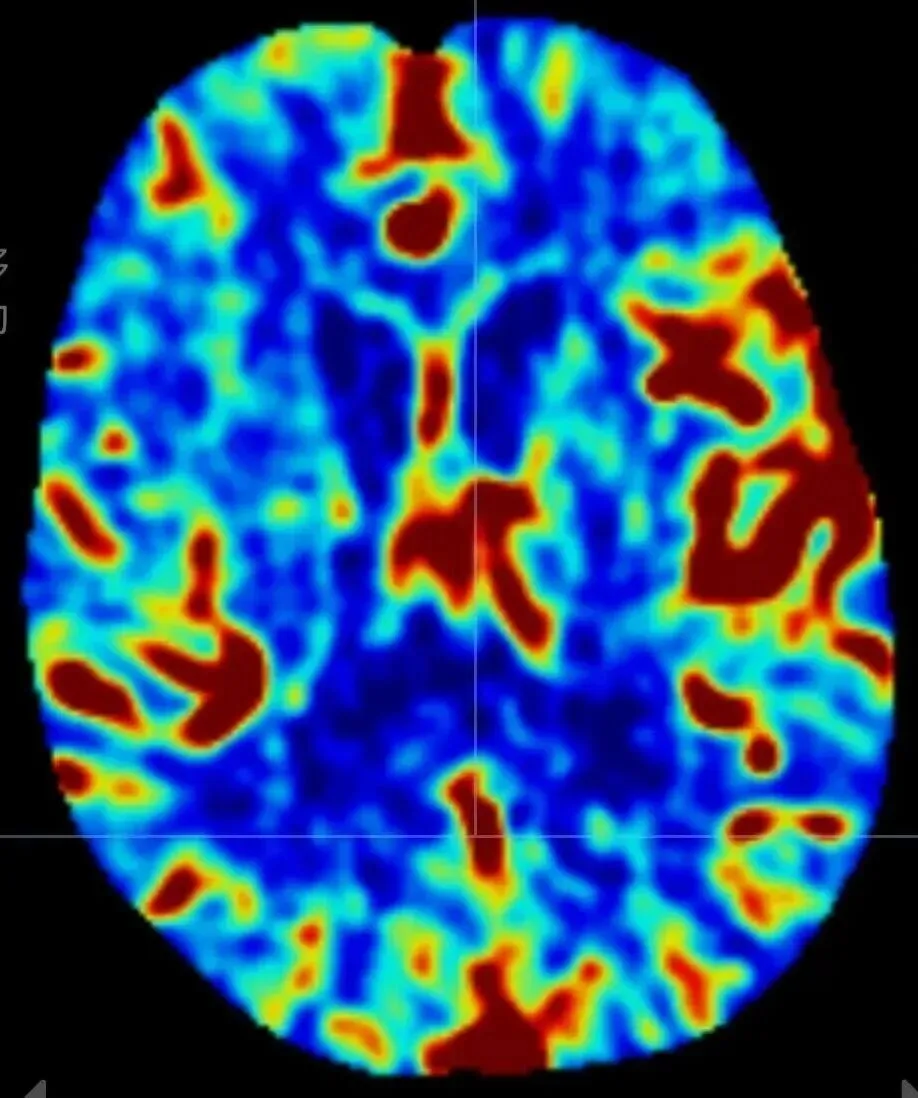

脑灌注成像分为CT灌注成像(CTP)、磁共振灌注成像(MRP)。利用CTP和MRP进行的灌注影像已经成为评估脑卒中患者脑血流灌注情况的常规手段。CT灌注成像(CTP)是指静脉注射对比剂的同时对选定的层面进行连续多次扫描,以获得该层面内每一个像素的时间-密度曲线。此项检查可限于一个兴趣区域,典型的有基底节区和侧脑室,因为其包含了前、中、后脑动脉供应的区域,也可包括全脑范围。 脑灌注成像中,不同颜色代表不同的血流情况(个人观点:理解了颜色含义,才能初步看懂灌注图像,否则不明白五颜六色是啥意思

),具体如下:

红色:代表血流量较高,通常出现在正常或健康的脑组织区域。

黄色:代表血流量适中,介于正常和异常之间,需进一步检查。

绿色:代表血流量低,出现在缺血或缺氧区域。

蓝色:代表血流量非常低,神经细胞功能可能受损。

黑色:代表完全无血流,通常出现在脑梗死或脑出血区域。